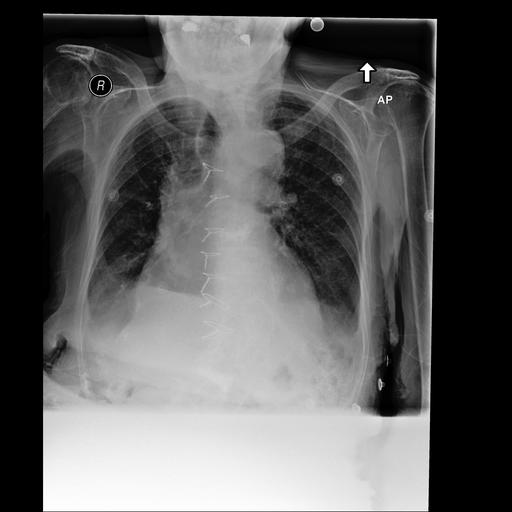

The second example (Table 5) illustrates behaviour in the SFT setting on MIMIC-CXR. The reference report describes low lung volumes and bibasilar opacities most likely representing atelectasis, and explicitly states the absence of pleural effusion or pneumothorax, with a stable and unremarkable cardiomediastinal silhouette.

Table 5: Qualitative Comparison in Supervised Fine-Tuning Setting or LLaVA-Med. Highlighting indicates: incorrect/hallucinated findings, incomplete descriptions, superfluous details, accurate content.

Supervised Fine-Tuned Setting

Chest X-Ray Image Ground Truth Report

[Uncaptioned image] Frontal and lateral views of the chest were obtained. There are low lung volumes which accentuate the bronchovascular markings. Bibasilar opacities are seen, which most likely represent atelectasis, although aspiration or infection are not excluded in the appropriate clinical setting. No pleural effusion or pneumothorax is seen. The cardiac and mediastinal silhouettes are stable and unremarkable.

SpLiCE Concepts: lateral view, lung base, volume low, left hemidiaphragm, appropriate clinical

Image-Only The heart size is normal. The hilar and mediastinal contours are normal. There is a new left lower lobe opacity, concerning for pneumonia. No pleural effusion or pneumothorax. The visualized osseous structures are unremarkable.

+ Concepts In comparison with the study of ___, there are lower lung volumes. Cardiac silhouette is within normal limits. Opacification at the left base is consistent with atelectatic changes and possible small effusion. In the appropriate clinical setting, superimposed pneumonia would have to be considered.

+ RAG The lungs are clear without focal consolidation. No pleural effusion or pneumothorax is seen. The cardiac and mediastinal silhouettes are unremarkable.

+ CEMRAG Lung volumes are low. Mediastinal and hilar contours are unremarkable. Pulmonary vasculature is not engorged. Patchy opacities in the lung bases likely reflect areas of atelectasis. No pleural effusion or pneumothorax is present. No acute osseous abnormality is visualized.

The Image-Only baseline captures part of this picture: it correctly rules out pleural effusion and pneumothorax and describes normal cardiac and mediastinal contours, but introduces a clinically relevant error by emphasising a new left lower lobe opacity concerning for pneumonia and omitting any mention of low lung volumes. This combination of partial correctness and misplaced emphasis is consistent with the moderate CheXbert Micro-F1 and F1-RG achieved by the SFT baseline in Table 2. With Concepts augmentation, the model more faithfully reflects the ground truth: it explicitly recognises lower lung volumes and describes left basal opacification as atelectatic change, while conditionally mentioning possible pneumonia “in the appropriate clinical setting”, closely echoing the phrasing of the reference report. The main discrepancy is the mention of a possible small effusion, which is explicitly ruled out in the ground truth. Overall, this aligns with the observed improvements in F1-RG and sequence-level metrics under SpLiCE. In the RAG-only condition, the report fails to mention the bibasilar opacities and instead states that the lungs are clear without focal consolidation. This represents a clinically concerning omission and is consistent with a failure mode in which the model appears to rely too heavily on retrieved studies and does not fully ground its description in the current image. The combined CEMRAG report strikes a better balance: it correctly identifies low lung volumes and patchy basal opacities likely reflecting atelectasis, preserves the correct absence of pleural effusion and pneumothorax, and maintains a coherent description of the cardiomediastinal silhouette. This progression from baseline to CEMRAG mirrors the quantitative gains reported for MIMIC-CXR and qualitatively illustrates how concept-level signals can prevent complete omission of pathologies when retrieval alone is unreliable.